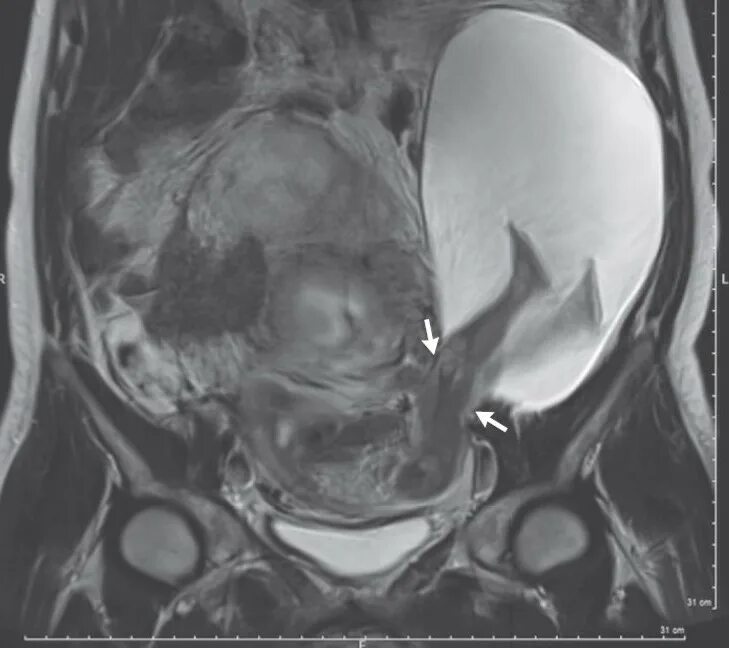

Разорвал матку